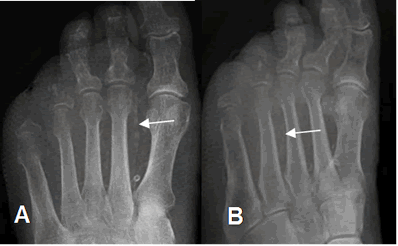

Fig 126 A. Pie diabético.

A: Rx AP y B: Rx oblicua del pie. Ausencia de las falanges del 4º y 5º dedo, por amputaciones previas. Calcificación en las paredes de los vasos, por angiopatía diabética. (Flechas).